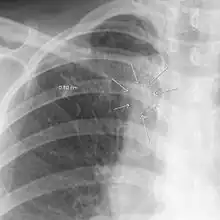

| The arrows denote an ill-defined nodular opacity in medial aspect of right upper lobe with ill-defined rim of lucency surrounding it | |

In radiology, the air crescent sign is a finding on chest radiograph and computed tomography that is crescenteric and radiolucent, due to a lung cavity that is filled with air and has a round radiopaque mass.[1] Classically, it is due to an aspergilloma, a form of aspergillosis, that occurs when the fungus Aspergillus grows in a cavity in the lung.[2] It is also referred as Monad sign.[3]